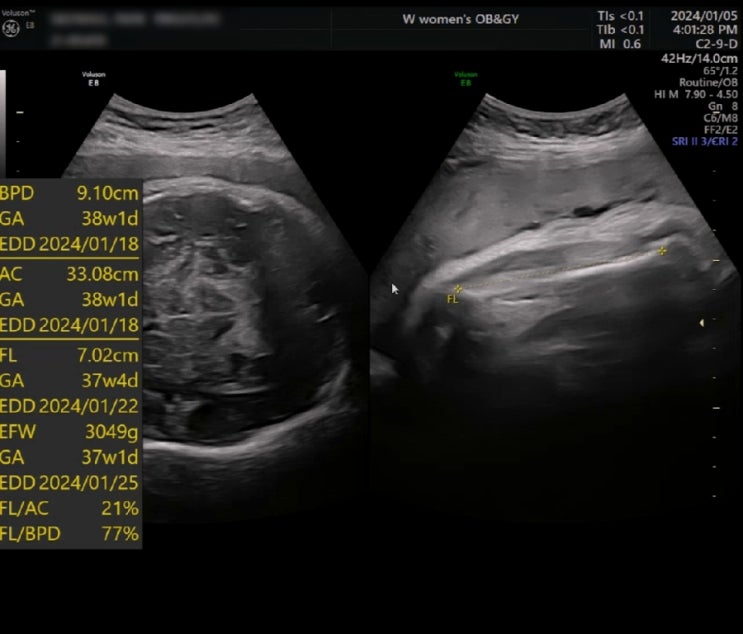

2024년 1월 15일 산모와 아이 모두 건강하게 출산 했습니다. 임신 막달에는 부종과 두통이 심해져서 평소처...